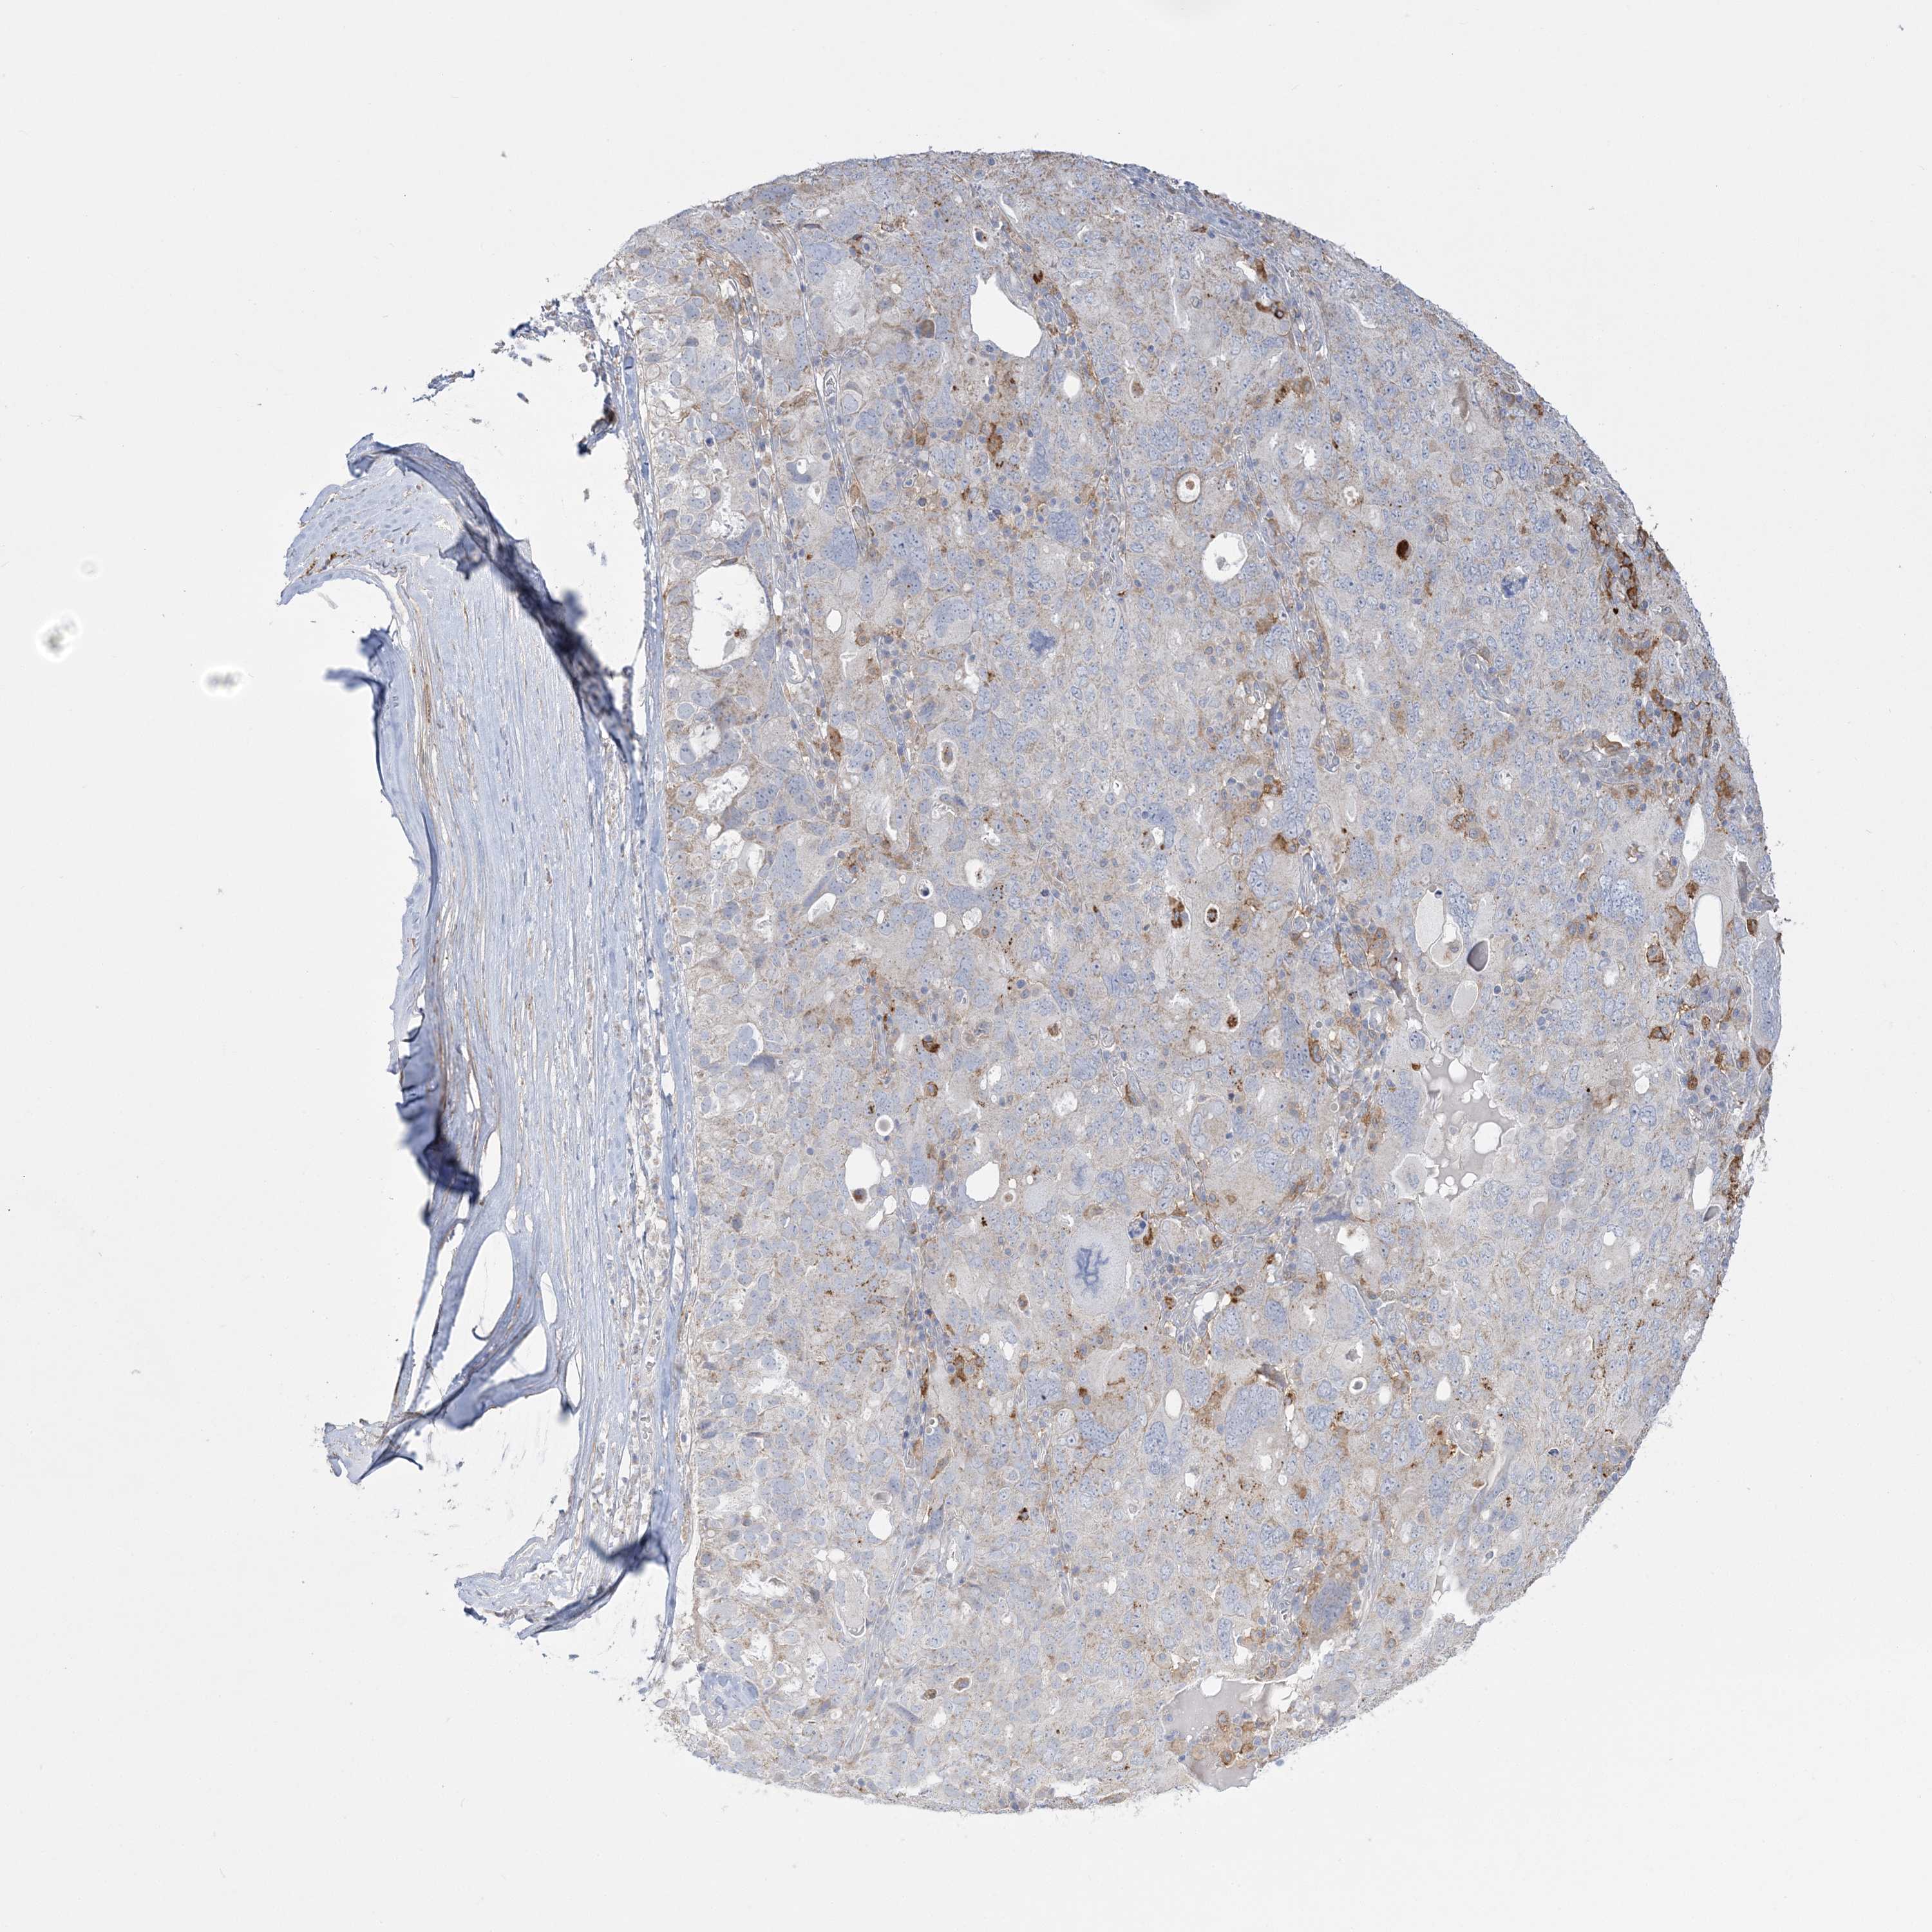

OVARIAN CANCER - Protein expressioni

A mouse-over function shows sample information and annotation data. Click on an image to view it in a full screen mode. Samples can be filtered based on level of antibody staining by selecting one or several of the following categories: high, medium, low and not detected. The assay and annotation is described here.

Note that samples used for immunohistochemistry by the Human Protein Atlas do not correspond to samples in the TCGA dataset.

Antibody stainingi

Antibody staining in the annotated cell types in the current human tissue is reported as not detected, low, medium, or high, based on conventional immunohistochemistry profiling in selected tissues. This score is based on the combination of the staining intensity and fraction of stained cells.

Each image is clickable and will lead to virtual microscopy that enables deeper exploration of all samples and also displays staining intensity scores, fraction scores and subcellular localization as well as patient and tissue information for each sample.

Antibody HPA036394

Antibody HPA042024

Cystadenocarcinoma, serous, NOS

Carcinoma, endometroid

Cystadenocarcinoma, mucinous, NOS

Carcinoma, NOS